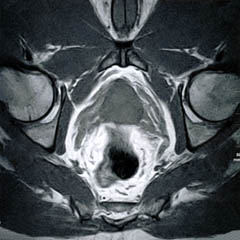

The Prostate without an Endorectal Probe |

| Prostate: Delineation of Peripheral Zones (PZ), Cortical Zone (CZ) and Vescicles without an Endorectal Coil. | |

Bladder

and Uterus in Pelvic Floor Dysfunction (PFD) |